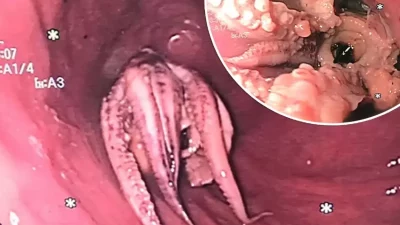

RADARBEKASI.ID, SINGAPURA – Tenggorokan merupakan anggota tubuh yang menjalar dari belakang hidung sampai ke bagian…

Susah Menelan